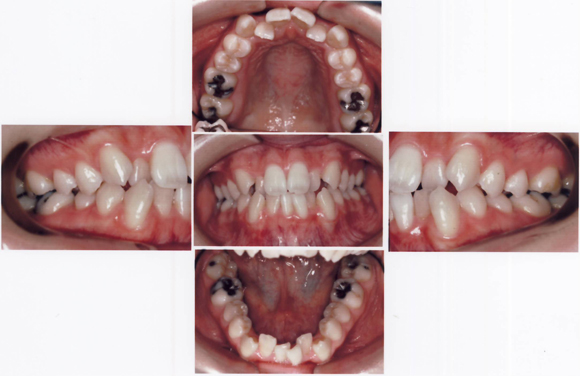

CASE4 乱杭歯(歯がひどく不揃いに生えている:八重歯や叢生も含む)ケース

術前

![]()